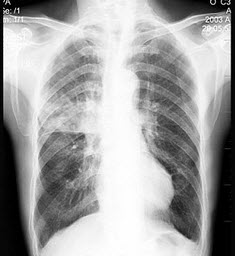

3、单项选择题

患者输液过程中突发胸闷,气急,咳痰,胸部正侧位片如图,最可能的诊断为()

A.硅沉着病合并感染

B.中央型肺水肿

C.真菌感染

D.间质性肺水肿

E.腺病毒肺炎